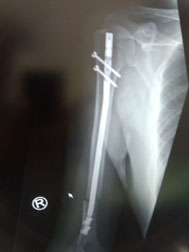

○上腕骨骨幹部骨折

二の腕を骨折してしまいました。救急で運ばれましたが、直ぐに処置はなく一週後に手術を受けました。骨にボルトを埋め込み固定する大手術です。

当患者さんは三週間が過ぎたころ、「痛みで夜まったく眠れない、痛み止めも全く効かない、

どうにかして下さい」と訴えて来られました。

見ると肘の周りが、かなりうっ血していて前腕の筋肉もコチコチになっていました。肩の関節の可動域もかなり制限されていました。当院ではまだ新鮮な術後だったので骨折部には触れず周りの皮膚を軽く軽擦(マッサージ)して、血腫には超音波治療をしました。するとみるみる痛みが軽減し夜も眠れるようになりました。整形外科の先生方は最新の治療で処置してくれますが患者さんの日常の苦しみにあまり耳を傾けてくれないようです。

手術後三角筋で固定 肘の周りに血腫(血が固まり)があり前腕の筋肉もカチカチになっていました。

また血腫による前腕部の圧力のためか神経麻痺の症状がありました。

前骨間神経麻痺と言って親指と人差し指の第一関節が屈曲できない症状です。